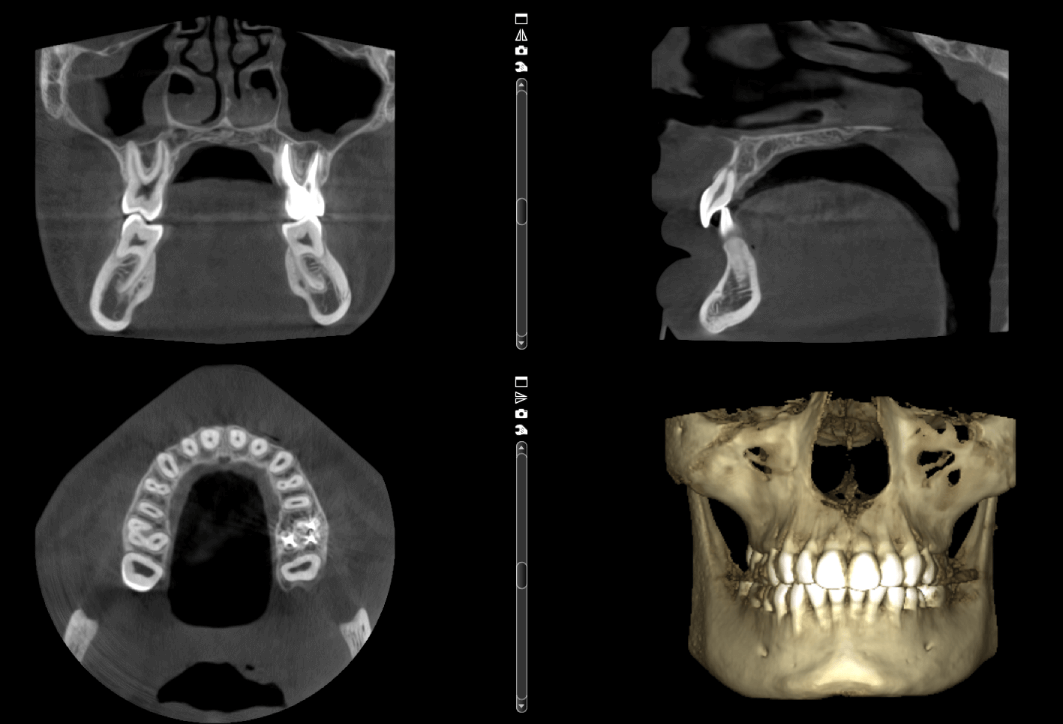

La colocación de implantes dentales es un procedimiento que requiere una planificación precisa. En nuestra clínica de radiología dental en

Una cirugía guiada se trata de un procedimiento asistido por ordenador en el que, a partir de un escaneo CBCT